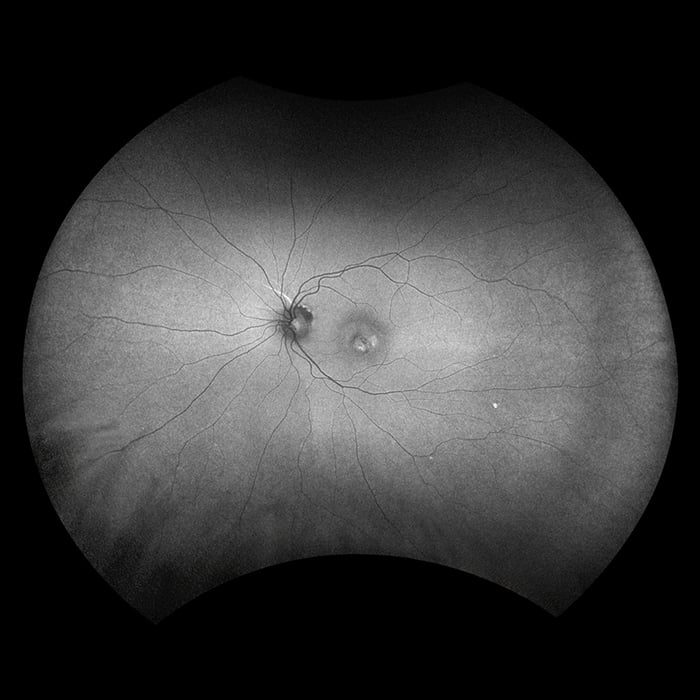

A non-invasive technique, autofluorescence was developed over the last decade to study the fluorescent properties of lipofuscin, which is a mixture of autofluorescent pigments that accumulate in the retinal pigment epithelium as a byproduct from the incomplete degradation of photoreceptor outer segments. AF imaging gives information over and above conventional imaging techniques such as fundus photos or fluorescence angiography as it allows visualization of the metabolic changes at the level of the RPE and helps to identify areas that may be at high risk for the development of geographic atrophy or CNV.